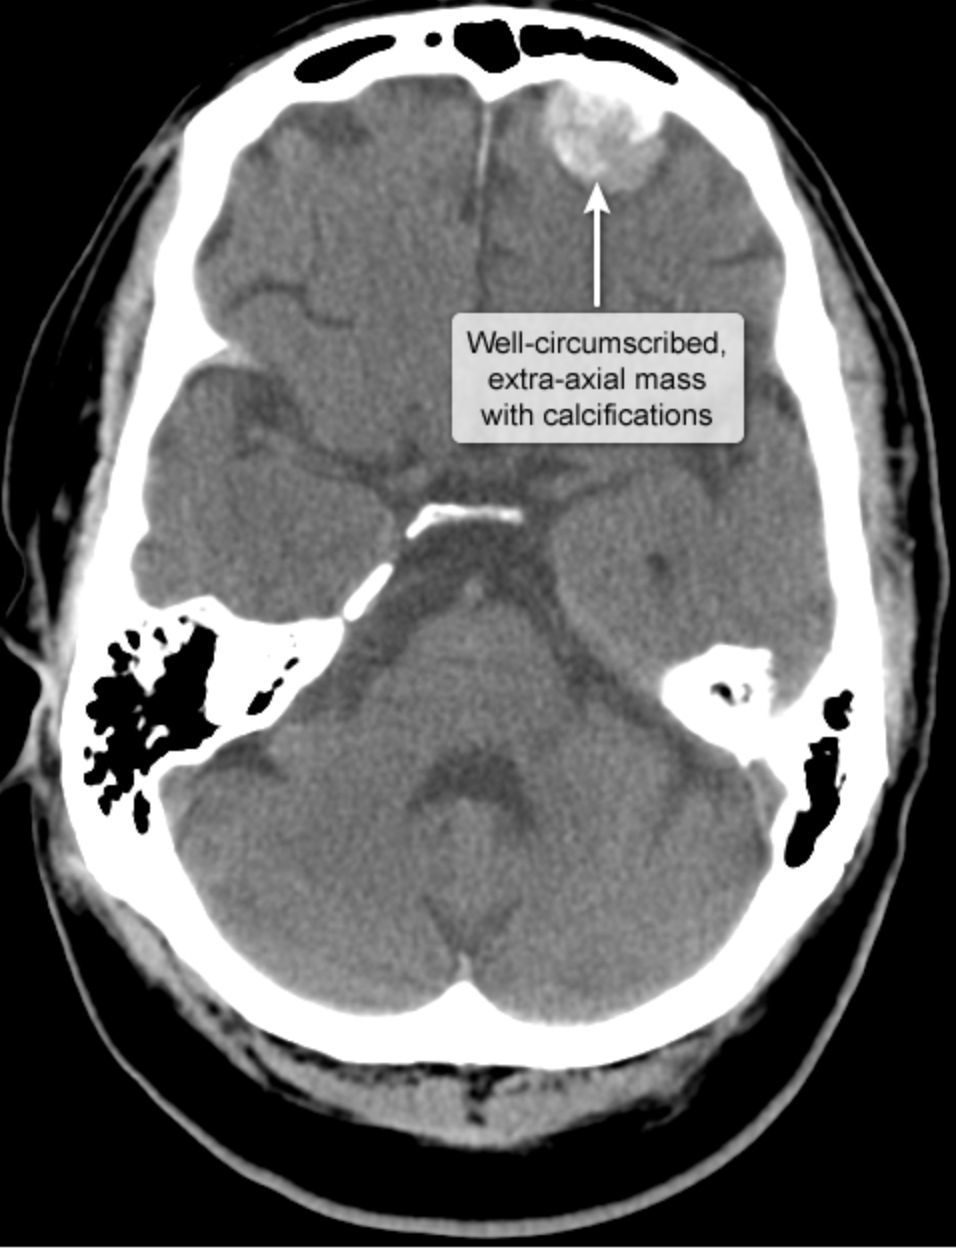

“Extra-axial, well-circumscribed, dural-based brain mass that enhances with contrast”

Meningioma desciption

Benign tumors, but may cause compressive symptoms

Resect surgically.